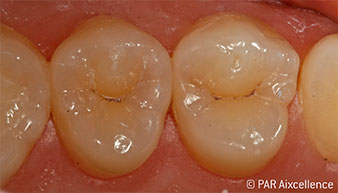

Рис. 1. Начальный вид зубов без клинических признаков кариеса